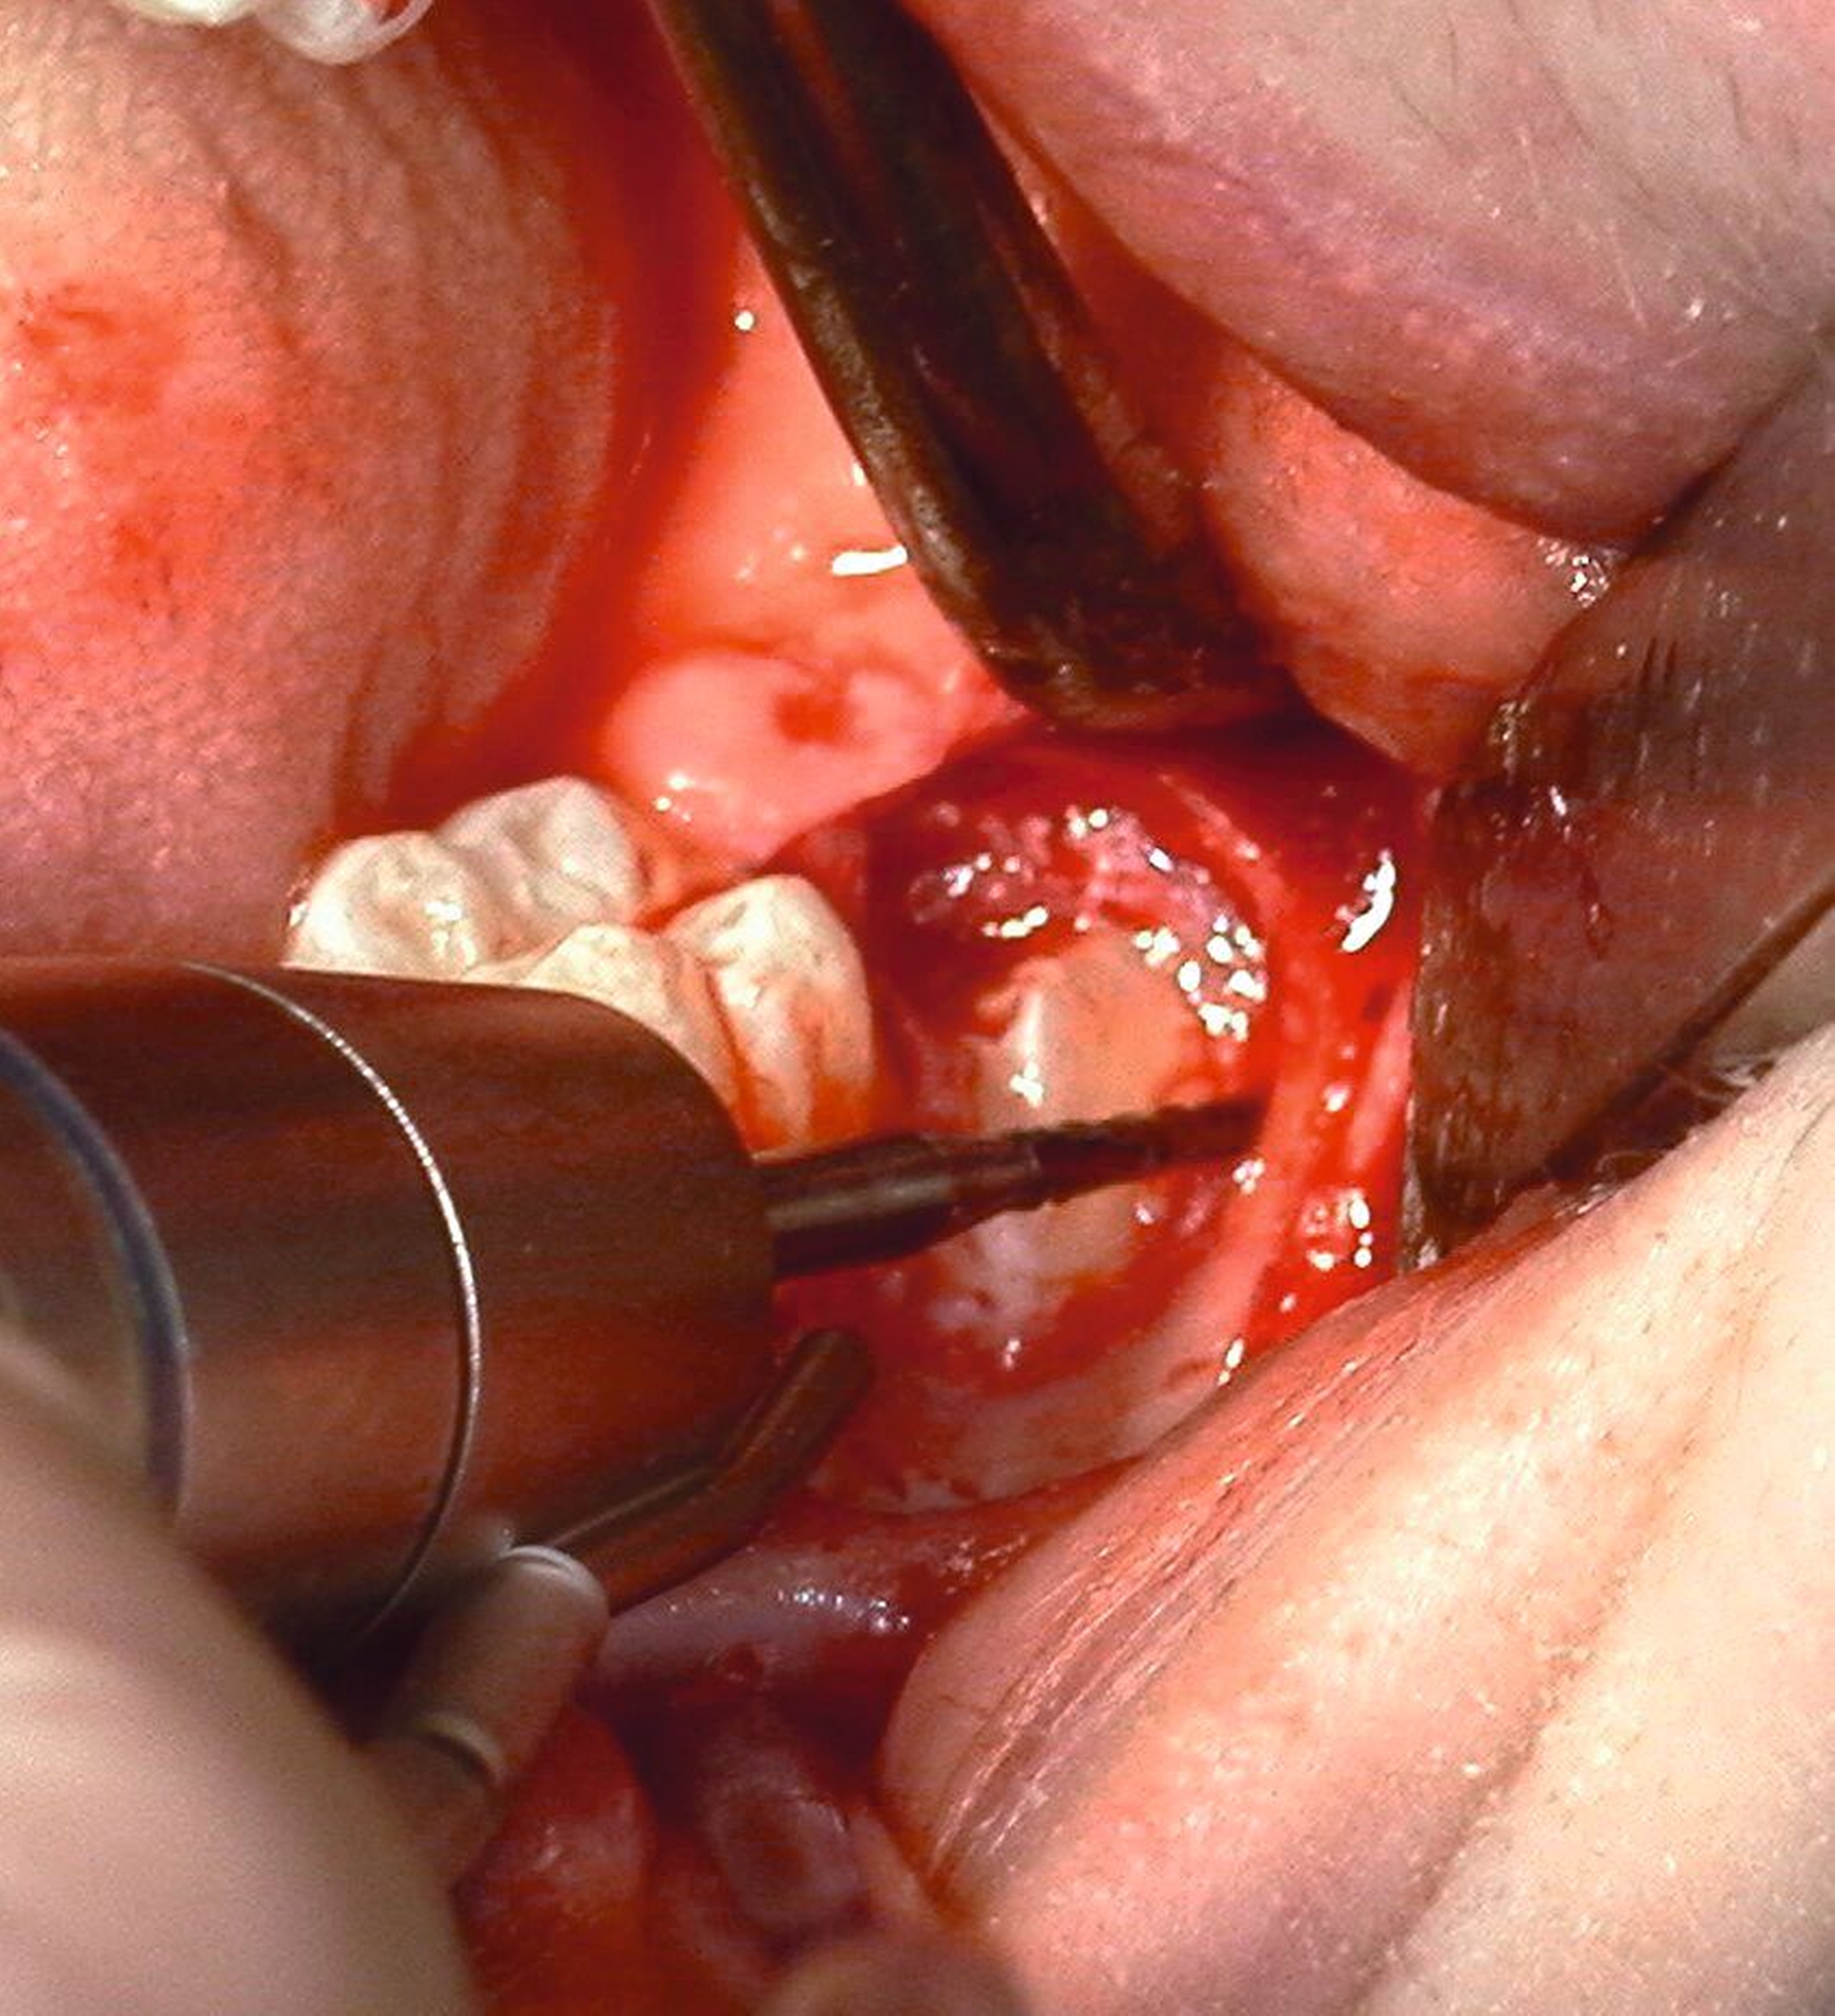

Nach Freilegung des Knochens kann ein Wundhaken nach Langenbeck eingesetzt werden sowie ein Bohr-Raspatorium zum Schutz des N. lingualis subperiostal lingual [Gutwald et al., 2019]. Unter Verwendung eines rotierenden Instruments (Kugel- und Lindemann-Fräse) oder Piezochirurgie wird der Knochen im Bereich der Zahnkrone abgetragen und diese freigelegt (Abbildung 8). Danach kann der Weisheitszahn vorsichtig mithilfe eines Bein‘schen Hebels anluxiert oder, falls dies noch nicht gelingt, mittels einer Lindemann-Fräse geteilt werden. Dabei wird am größten Kronendurchmesser die Krone mit der Fräse abgetrennt und die Wurzel anschließend separat entfernt (Abbildungen 9 und 10) [Gutwald et al., 2019; Schwenzer, 2019].